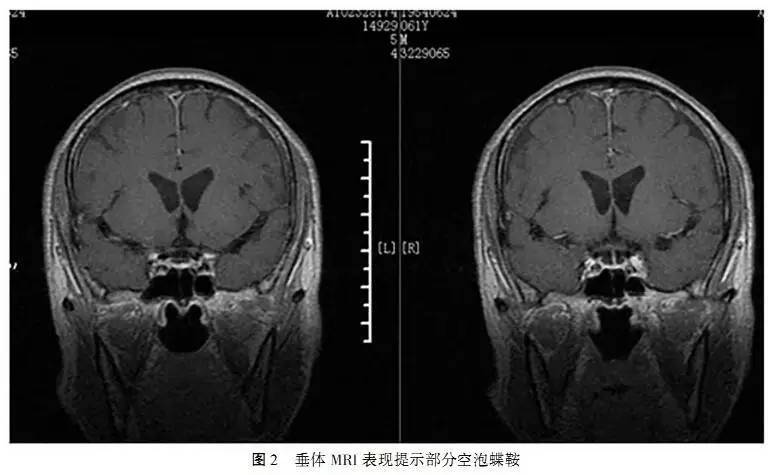

患者3次血尿同步电解质及血尿渗透压结果见表1,发现2次尿钠和尿氯排出增多,2次尿渗透压增高,1次血渗透压降低,另有1次血钠稍偏低(133mmol/L,与减少口服盐胶囊有关)。其余检查包括红细胞压积、肝肾功能、血气分析、甲状腺功能、肾上腺功能、立卧位试验、过夜1mg地塞米松抑制试验、性激素均正常。脑钠肽(BNP)及脑钠肽原(proBNP)也正常。患者入院后复查头颅CT提示:双侧额顶叶、脑室周边白质缺血灶、左小脑软化灶(图1)。垂体MRI提示:部分空泡蝶鞍(图2)。